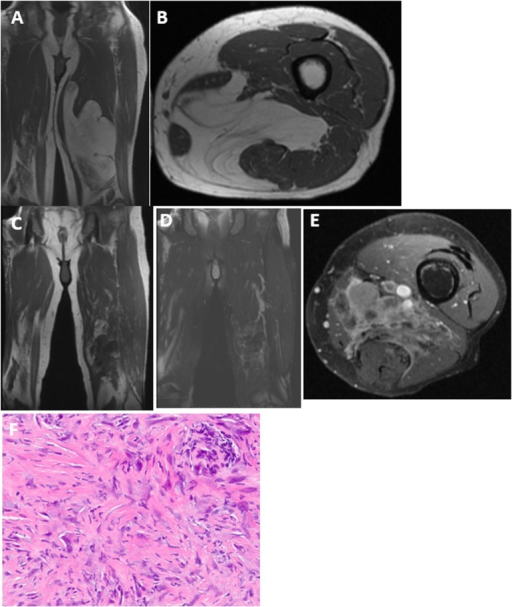

Axial T2-weighted MRI of the left thigh showing a large, heterogeneous soft tissue mass in the anterior compartment. The mass is well-circumscribed with high T2 signal and areas of necrosis. It displaces the femoral vessels but does not encase them. The size (>5cm), depth (deep to fascia), and heterogeneous appearance are concerning for high-grade sarcoma. Biopsy is required before treatment.